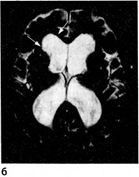

Рис. 2.2. Идиопатическая нормотензивная гидроцефалия.

а. Сагиттальный срез МРТ головного мозга в Τ1-режиме,

б. Аксиальный срез МРТ головного мозга в Т2-режиме. Стрелками показано расширение боковых желудочков.

Нейровизуализация играет важную роль в диагностике одной из потенциально обратимых форм деменции – нормотензивной гидроцефалии. При этом KT или МРТ головного мозга выявляет преимущественно внутреннюю гидроцефалию, максимально выраженную в области передних рогов боковых желудочков (рис. 2.2).